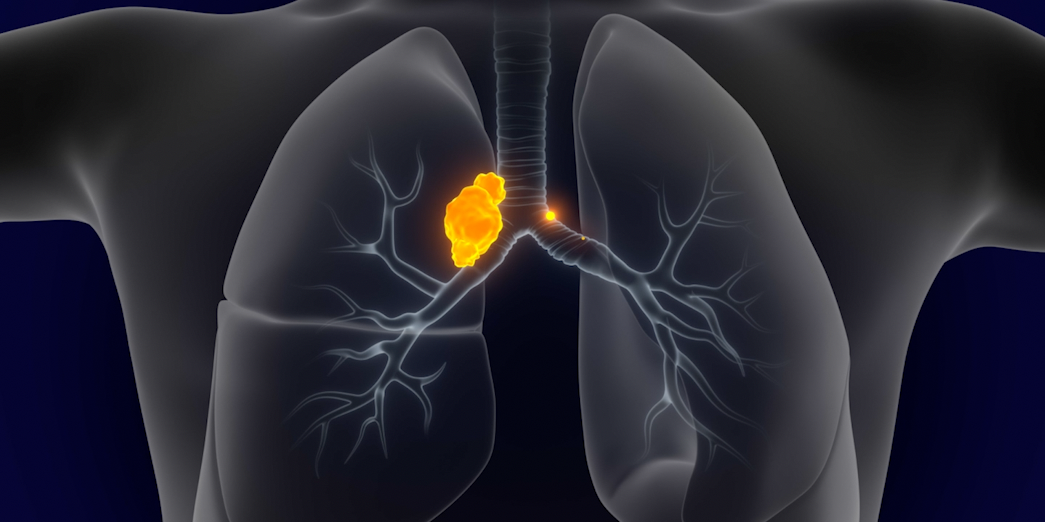

Learn about expanding options to delay relapse after induction.

1L TREATMENT- Rudin CM, Brambilla E, Faivre-Finn C, Sage J. Small-cell lung cancer. Nat Rev Dis Primers. 2021;7(1):3. doi:10.1038/s41572-020-00235-0

- Byers LA, Rudin CM. Small cell lung cancer: where do we go from here? Cancer. 2015;121(5):664-672.

- Huber RM, Tufman A. Update on small cell lung cancer management. Breathe. 2012;8(4):314-330.

- Small cell lung cancer stages. American Cancer Society. https://www.cancer.org/cancer/lung-cancer/detection-diagnosis-staging/staging-sclc.html. Accessed March 25, 2025.